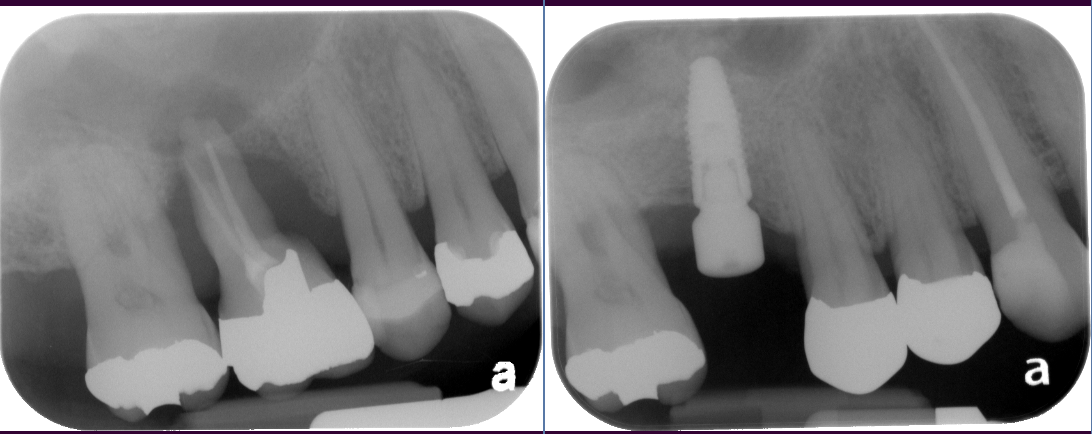

The key to a successful and long-lasting dental implant is the quality and quantity of jaw bone to which the implant will be attached. If bone loss has occurred due to injury or periodontal disease, a sinus augmentation can raise the sinus floor and allow for new bone formation.

In the most common sinus augmentation procedure, a small incision is made on the premolar or molar region to expose the jaw bone. A small opening is cut into the bone, and the membrane lining the sinus is pushed upward. The underlying space is filled with bone grafting material, either from your own body or from a cadaver. Sometimes, synthetic materials that can imitate bone formation are used. After the bone is implanted, the incision is stitched up and the healing process begins.

After several months of healing, the bone becomes part of the patient’s jaw and dental implants can be inserted and stabilized in this new sinus bone.

If enough bone between the upper jaw ridge and the bottom of the sinus is available to stabilize the implant well, sinus augmentations and implant placement can sometimes be performed as a single procedure. If not enough bone is available, the sinus augmentation will have to be performed first, then the graft will have to mature for several months, depending upon the type of graft material used. Once the graft has matured, the implants can be placed.

The bone used in a sinus lift may come from your own body (autogenous bone), from a cadaver (allogeneic bone) or from cow bone (xenograft). You will need X-rays taken before your sinus lift so the dentist can study the anatomy of your jaw and sinus. You also may need a special type of computed tomography (CBCT) scan. This scan will allow the dentist to accurately measure the height and width of your existing bone and to evaluate the health of your sinus.